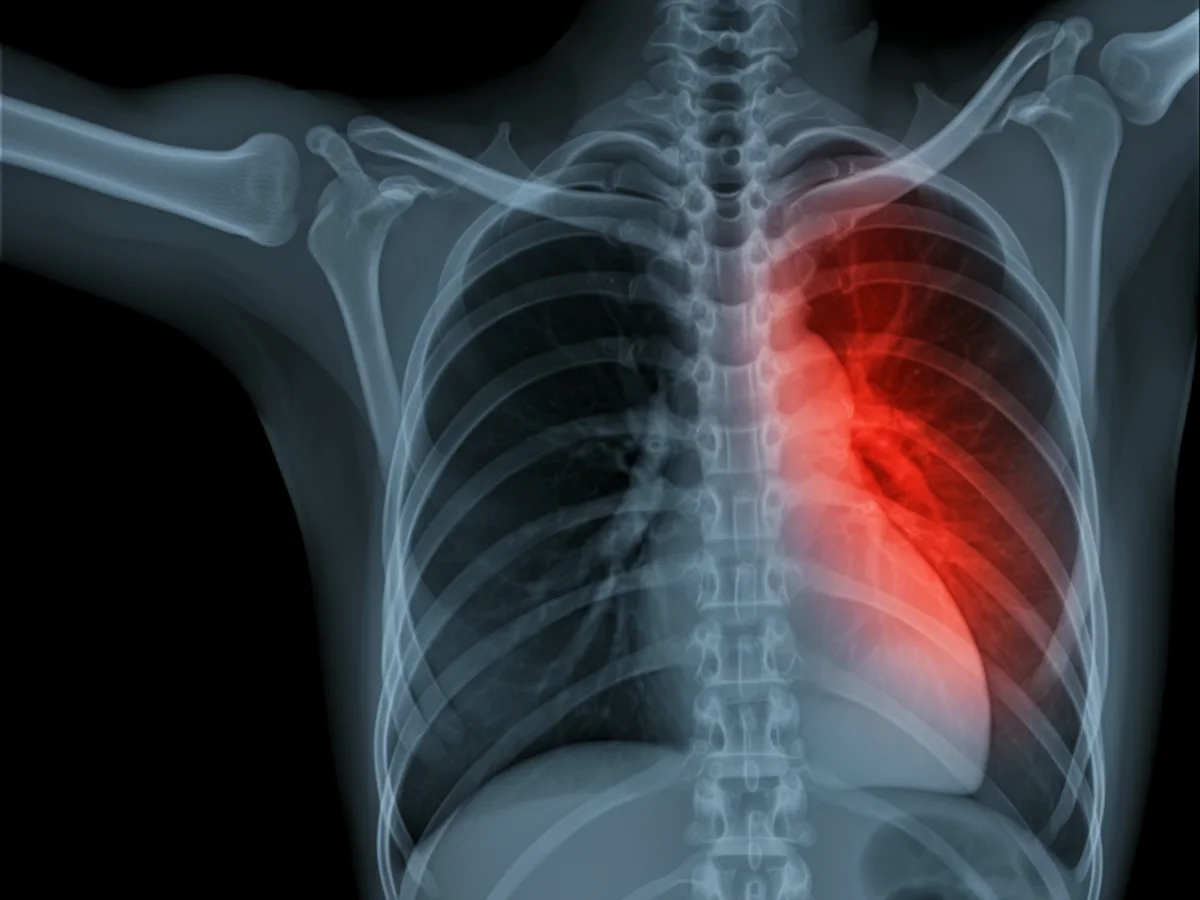

Die Diagnose von felinem Asthma erfolgt meist durch eine Kombination aus klinischer Untersuchung und speziellen Tests: